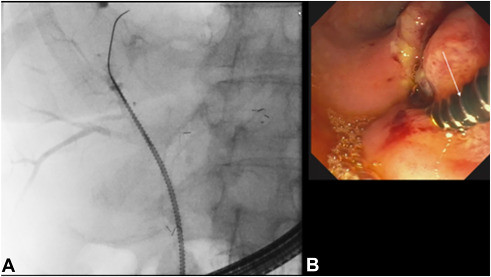

Fluoroscopic (A) and endoscopic images (B) showing a 7F spiral drill dilator (Tornus ES; Asahi Intecc Co, Aichi, Japan) (arrow) inserted over a 0.025-inch guidewire through the mesh of the left hepatic stent into the right anterior sector.

We present a case of endoscopic management of malignant hilar biliary obstruction (Bismuth type IIIa cholangiocarcinoma) in a 74-year-old woman using dual-sector uncovered metal stent placement in a stent-in-stent (Y) configuration. After successful placement of a left hepatic stent, access to the right anterior sector was achieved with a guidewire.

However, standard devices, including a balloon catheter and stent delivery system, were unable to traverse the mesh of the first stent across a high-grade stricture. A spiral drill dilator (Tornus ES; Asahi Intecc Co, Aichi, Japan) was then used with controlled clockwise rotation to gently create a tract through the stent mesh and stricture. This enabled successful passage into the right anterior sector and placement of a second uncovered metal stent, completing the Y configuration and achieving effective dual-sector biliary drainage.